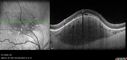

Amelanotic Nevus - OCT findings

60 year old man with normal vision. Nevus is 1 mm tall and was stable over 6 years follow-up

Amelanotic Choroidal Nevus352 views60 year old man. Nevus is stable over 6 years. Images are Photo, FAF, OCT, FA, ICG, and B-Scan     (0 votes)